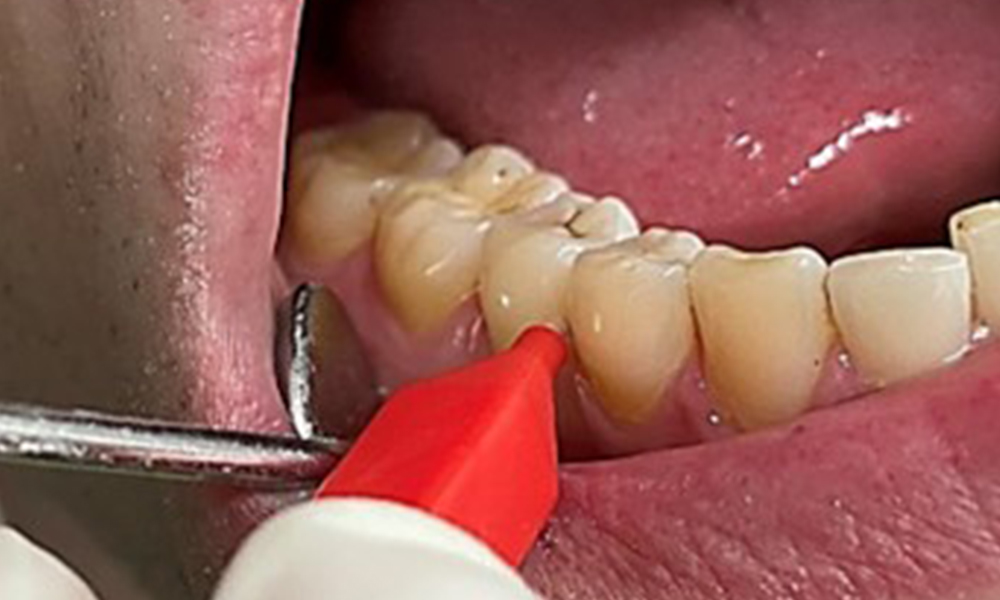

The objective would be to control disease risk by removing supragingival and subgingival biofilm. The instruments can be selected based on patient needs. First, calculus and any concretions must be removed using ultrasonic and/or manual instruments (Fig. 10).